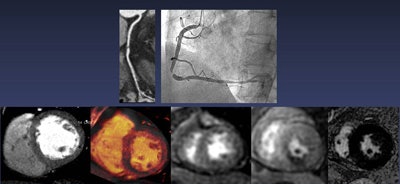

Left to right: Rest single-energy CT does not show perfusion defect in left ventricular myocardium. Stress DECT shows perfusion defect in midinferoseptal and inferior wall, corresponding to right coronary artery territory. Rest and stress perfusion MRI confirmed the reversible perfusion defect in right coronary artery territory. No myocardial infarction was seen in the left ventricular wall on delayed contrast-enhanced MRI. Image courtesy of Dr. Sung Min Ko.| Detection of ischemia-causing coronary artery stenoses | |||

| DECT-MPI and CCTA | DECT-MPI alone | CCTA alone | |

| Sensitivity | 88% | 91% | 95% |

| Specificity | 82% | 75% | 45% |

| PPV | 79% | 75% | 63% |

| NPV | 89% | 92% | 94% |

The area under the receiver operator characteristics curve for DECT-MPI and CCTA was 0.85, compared with 0.75 for CCTA alone (p = 0.001).